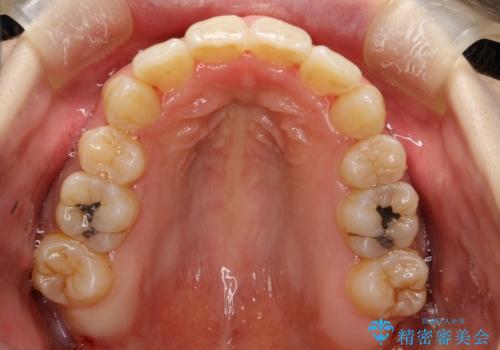

重度のガタガタ ワイヤーによる抜歯矯正

- 出っ歯と全体的ながたつきを主訴に来院されました。

上下の歯に重度のガタガタがあり、前歯が下の歯と咬んでいない状態でした。

審美装置を用いた、抜歯矯正を行うこととしました。